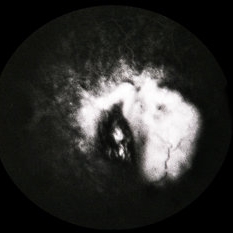

RPE Tear

RPE Tear

Sep 9 2014 by David Callanan, MD

78-year-old male, RPE tear.

Condition/keywords: retinal pigment epithelium